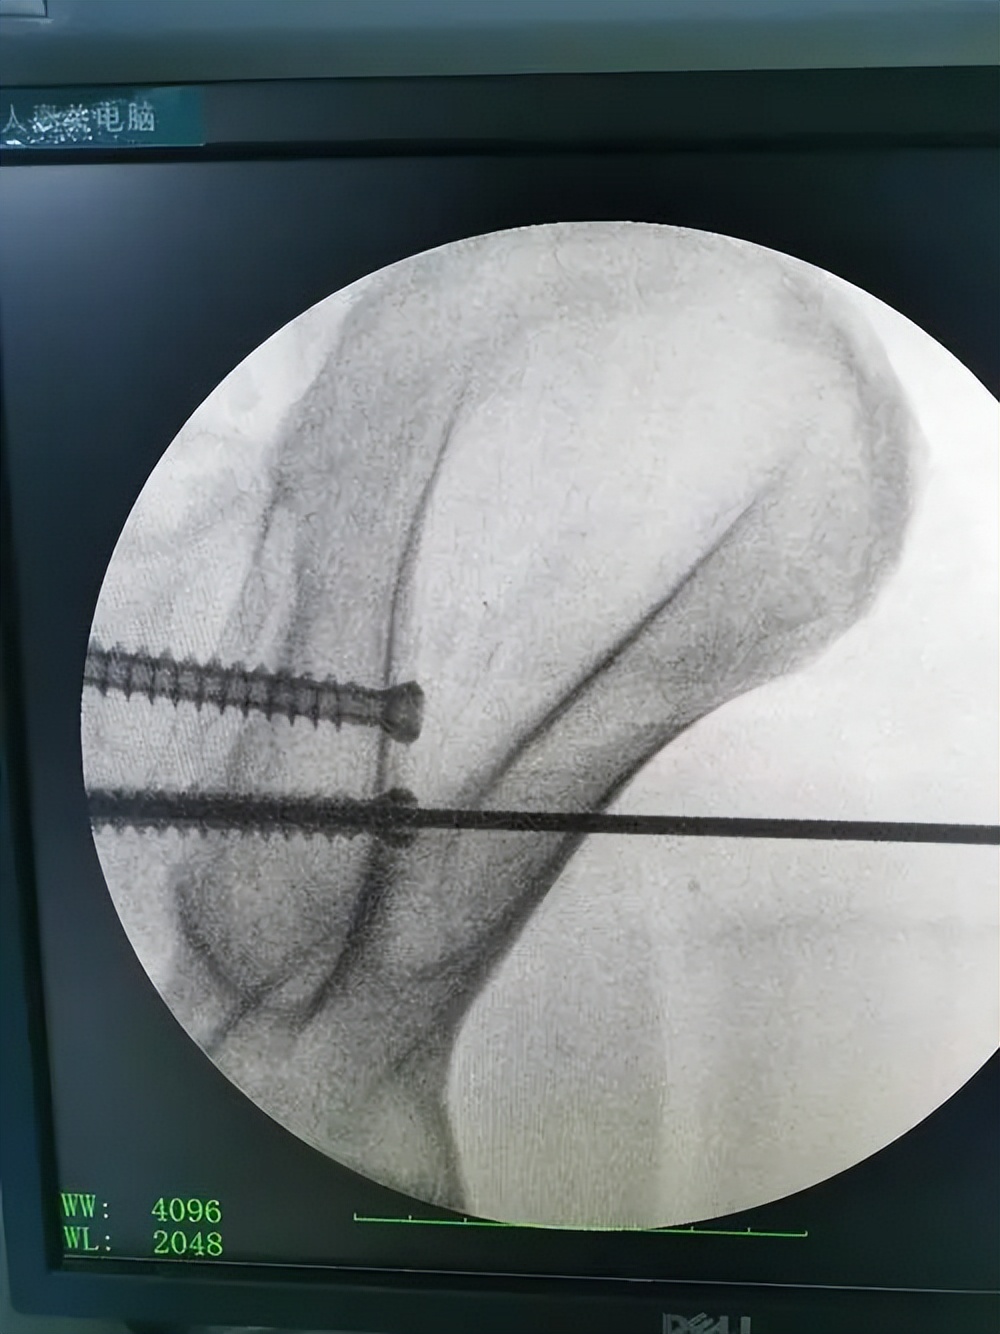

IS固定具有固定效果可靠以及可进行微创操作等优点, 1989年时Matta等人第一次报道在骨盆后环损伤患者中使用骶髂螺钉固定,并且,到如今,此方法仍然是目前临床治疗骨盆后环损伤最常用的方法之一。

IS固定技术可减少患者创伤,同时手术时间大大缩短,术后感染风险也大幅减少。 但是,在IS操作过程中需要反复透视定位钉道位置,骶髂拉力螺钉的长度以及直径选择不当的话就有可能对重要神经造成损伤,出现不可挽救的并发症。

但由于和其他内固定方式相比,此内固定方式更能体现出微创理念,并且感染风险小,操作简单,固定牢固,故仍然常被使用。

在固定时,是否需要2枚螺钉固定还存争议。在骨盆前环稳定固定后,后环是否使用2枚螺钉固定并无差别。通过生物力学分析证明,前环不稳时,2枚螺钉的固定效果优于1枚螺钉。

从生物力学稳定方面来看, 两枚骶骼螺钉的固定效果要优于单枚拉力螺钉固定,因为单枚拉力螺钉无法做到对抗旋转移位或者对抗旋转移位的能力小。

但是,植入两枚拉力螺钉时发生血管神经并发症的可能性更高。 研究发现在植入骶骼关节拉力螺钉时,髂血管以及骶神经仅需要4°的偏差就可被损伤。

故在行此内固定术时,还需要仔细制定手术方案,并且由经验丰富、对解剖知识以及解剖变异型熟知的医师进行手术操作。